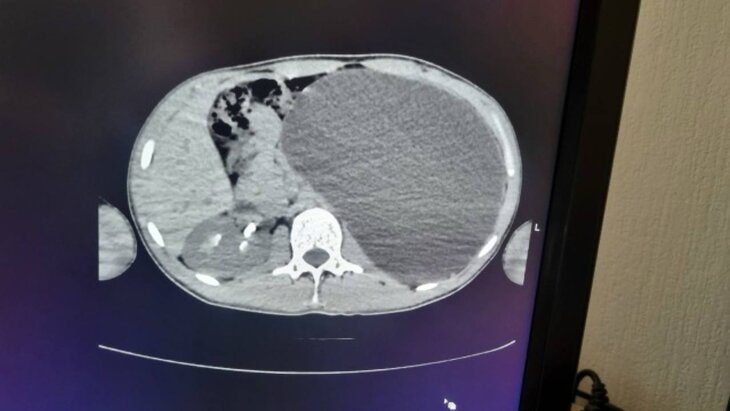

Врачи Новосибирска удалили 17-летнему юноше почку, раздувшуюся до размеров 5-литровой бутылки. Об этом сообщила пресс-служба регионального Минздрава.

"Мы стали обследовать, оказалось, что это гидронефроз левой почки с отсутствием паренхимы (основной ткани органа, выполняющей его функции. – Прим. ред.)", – добавила Живолуп.

"У нашего пациента почка достигла размеров пятилитровой бутылки! Она занимала почти весь объем живота и давила на все соседние органы. Это была настоящая бомба замедленного действия: любая травма, случайный удар в живот – и мешок мог разорваться внутри", – добавили в ДГКБ № 1.